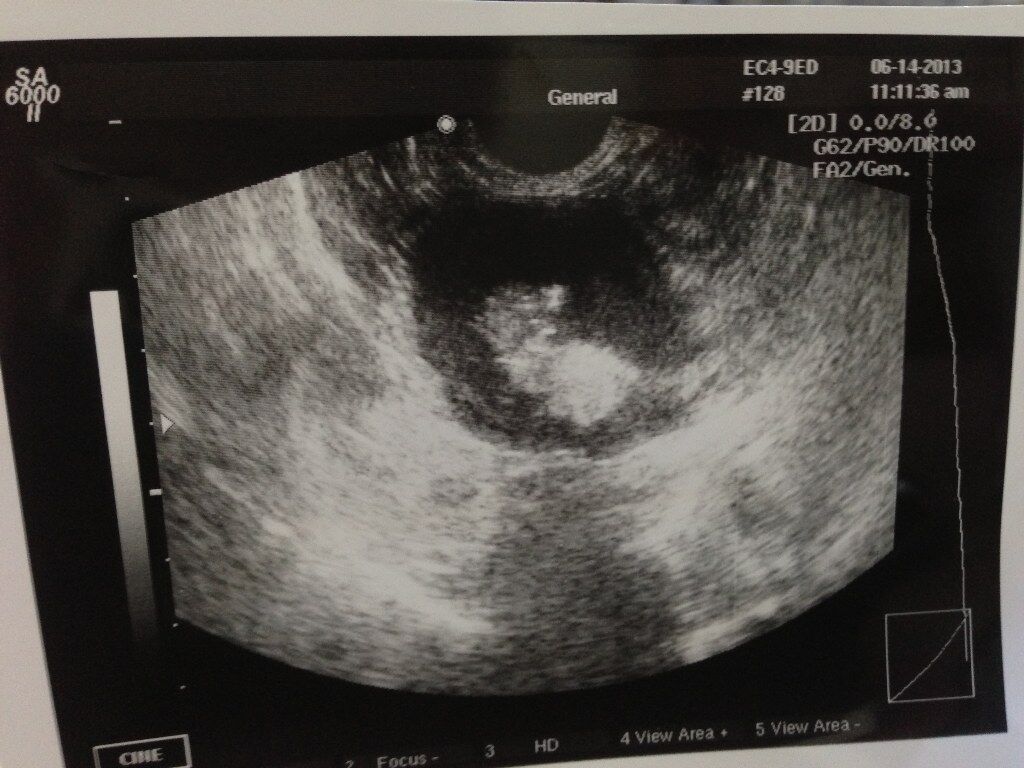

問題は腹部の腫瘤で、エコーとレントゲン写真を下に示します。

腹腔内に複数の腫瘤が認められましたので腸管膜のリンパ節が大きくなっていることが予想されました。飼い主さんと相談しまして、まずは開腹手術をして、切除できるものなら切除するということになりました。